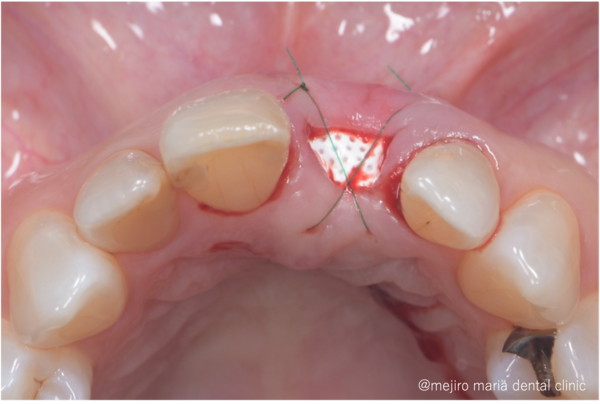

目白マリア歯科|歯周形成外科の症例|【症例】抜歯後の歯茎の凹みを低侵襲で予防し、接着性ブリッジを用いてインプラントを回避 歯槽堤保存術(Alveolar Ridge Preservation ; ARP) |切開後しょ

左側中切歯を抜歯し、抜いた穴の中を徹底的に綺麗にします。その後、骨の吸収を抑えるために人工骨を填入し、PTFEメンブレンという人工の膜でカバーし、縫合します。

丁寧で愛護的な抜歯と、適切な材料をチョイスすることで、術後の骨と歯茎のボリュームダウンを極力防ぐことができます。